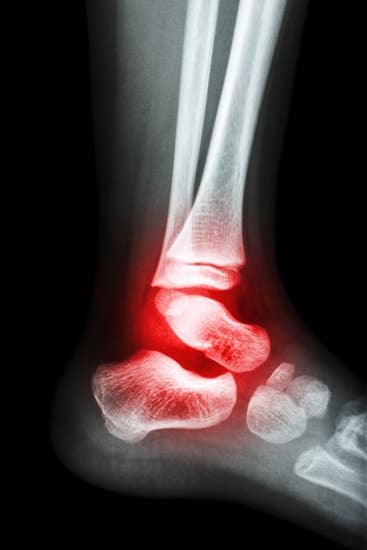

발목 관절염: 원인, 증상, 치료 및 관리

발목 관절염(Ankle Arthritis)은 발목 관절에 염증이 발생하여 통증과 부종, 관절의 움직임 제한을 일으키는 질환입니다.

이는 발목 관절의 연골이 손상되거나 마모되어 발생하며, 가장 흔한 형태로는 골관절염이 있습니다.

발목 관절염의 증상

발목 통증

발목 관절염의 대표적인 증상은 통증입니다. 초기에는 움직일 때만 통증이 느껴지지만, 질환이 진행됨에 따라 휴식 중에도 통증이 발생할 수 있습니다.